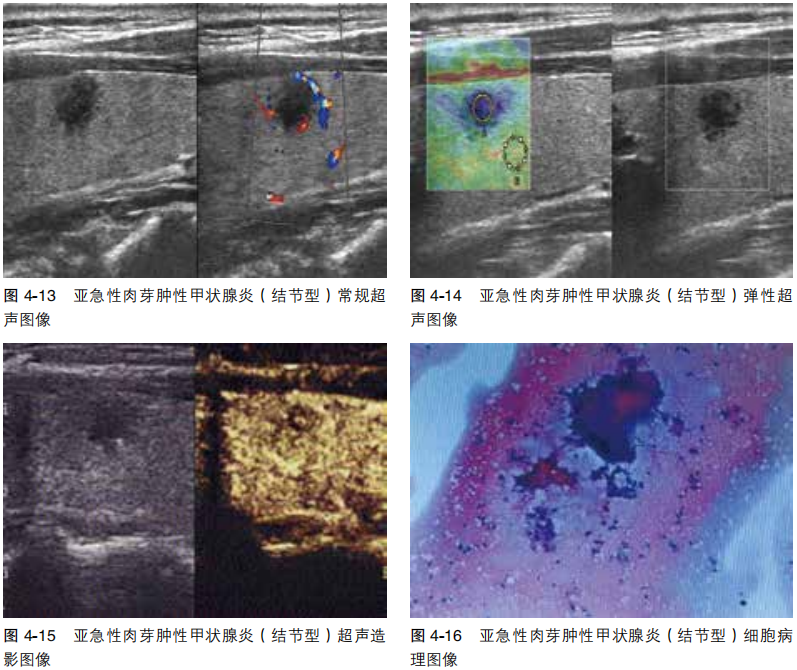

病例3

亚急性肉芽肿性甲状腺炎(结节型)

image.png

图像与特征

常规超 左叶实性结节,低回声,边缘多发毛刺,纵横比<1,无包膜,边界不清。

弹性超声 弹性评分4级。

超声造影 结节向心性增强,内呈低增强,范围大于二维范围,边界欠清

分析与诊断

常规超声 实性结节(2分),低回声(2分),边缘不规则(2分),纵横比<1,ACR TI-RADS 4类(6分),轻度可疑恶性结节,建议FNAC。

弹性超声 符合恶性结节。

超声造影 不符合典型良性结节表现,建议FNAC。

细胞病理 亚急性肉芽肿性甲状腺炎,BRAF V600E基因未见突变。

病例4

常规超声 左叶实性结节,低回声,边缘毛刺,纵横比>1,无包膜,边界不清。

超声造影 结节向心性增强,边缘等增强,中央少许低增强,范围略小于二维范围,边界欠清。

常规超声 实性结节(2分),低回声(2分),边缘不规则(2分),纵横比>1(3分),ACR TI-RADS 5类(9分),可疑恶性结节,建议FNAC。

超声造影 难以判定良恶性,不排除亚急性肉芽肿性甲状腺炎。

细胞病理 左叶亚急性甲状腺炎,BRAF V600E基因未见突变。

病例5

超声造影 结节早期向心性增强,呈均匀等增强,边界不清。

常规超 实性结节(2分),低回声(2分),边缘不规则(2分),纵横比>1(3分),ACR TI-RADS 5类(9分),可疑恶性结节,建议FNAC。

超声造影 符合良性结节改变。

细胞病理 左叶亚急性肉芽肿性甲状腺炎,BRAF V600E基因未见突变。

本例常规超声及弹性超声均提示恶性结节,超声造影符合良性病变表现,FNAC是可靠确诊方法。